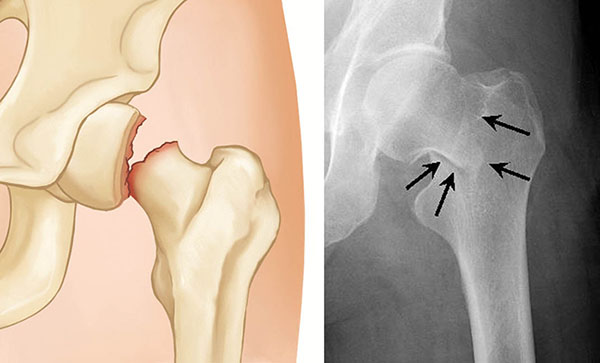

– Κάταγμα αυχένα του μηριαίου (ενδαρθρικό)

– Ακτινογραφία λεκάνης και ισχίου

– CT ή MRI (αν η ακτινογραφία δεν δείχνει κάταγμα αλλά τα συμπτώματα επιμένουν)